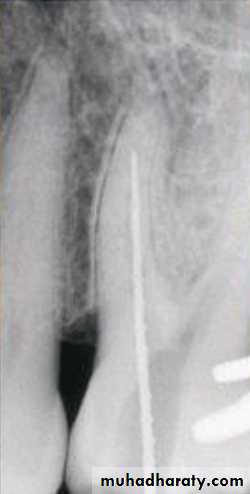

zipping

When a curved foramen is filed with pressure against the outer side of the curvature.

Repeated filing Zips and transport the foramen.